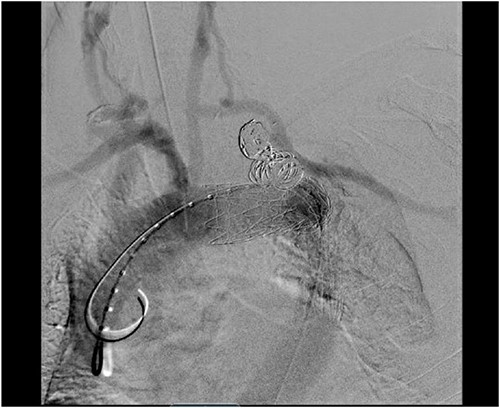

Staged operative repair was utilized, where the first stage involved LSA revascularization. The patient underwent a left common carotid artery to LSA bypass utilizing a 7-mm Dacron graft. We performed left vertebral artery transposition onto the bypass graft in an end-to-side fashion (Fig. 3). Intraoperative doppler confirmed biphasic signals through the bypass graft and vertebral artery. The second stage was performed 3 days post-operatively, which included TEVAR with stent graft placement and coverage of LSA. After bilateral percutaneous common femoral artery access was obtained, arch aortogram was completed, which showed patency of the common carotid to LSA bypass and left vertebral artery. Embolization of the left SAA was performed using multiple Terumo coils™ (framing coil, azur cx coil, peripheral coil and helical hydrocoil). Next, a Gore C-Tag graft measuring 34 × 34 × 150 mm was deployed in Zone 2, just proximal to the take-off of the left common carotid artery. Repeat arch aortogram showed complete exclusion of the left SAA with a patent left common carotid artery, left carotid-subclavian bypass and left vertebral artery (Fig. 4). There was no further filling of the left SAA.

Aortic arch angiogram showing patency of the left carotid to subclavian artery bypass graft with vertebral artery implantation and showing coil embolization of the proximal left SAA.